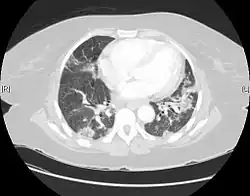

| CT scan of a patient with UIP. There is interstitial thickening, architectural distortion, honeycombing and bronchiectasis. | |

UIP may be diagnosed by a radiologist using computed tomography (CT) scan of the chest, or by a pathologist using tissue obtained by a lung biopsy.

Radiology

Radiologically, the main feature required for a confident diagnosis of UIP is honeycomb change in the periphery and the lower portions (bases) of the lungs.[3]

On high-resolution computed tomography (HRCT), the following categories, depending on imaging findings, have been recommended by a collaborative effort by the American Thoracic Society, European Respiratory Society, Japanese Respiratory Society, and the Latin American Thoracic Society:[4]

- UIP pattern:[4]

- Honeycombing, with or without peripheral traction bronchiectasis; or bronchiolectasis (dilatation of the terminal bronchioles)[5]

- Predominantly subpleural and basal

- Often heterogenous distribution, being occasionally diffuse, and may be asymmetrical

There may be superimposed CT features such as mild ground-glass opacity, reticular pattern and pulmonary ossification.